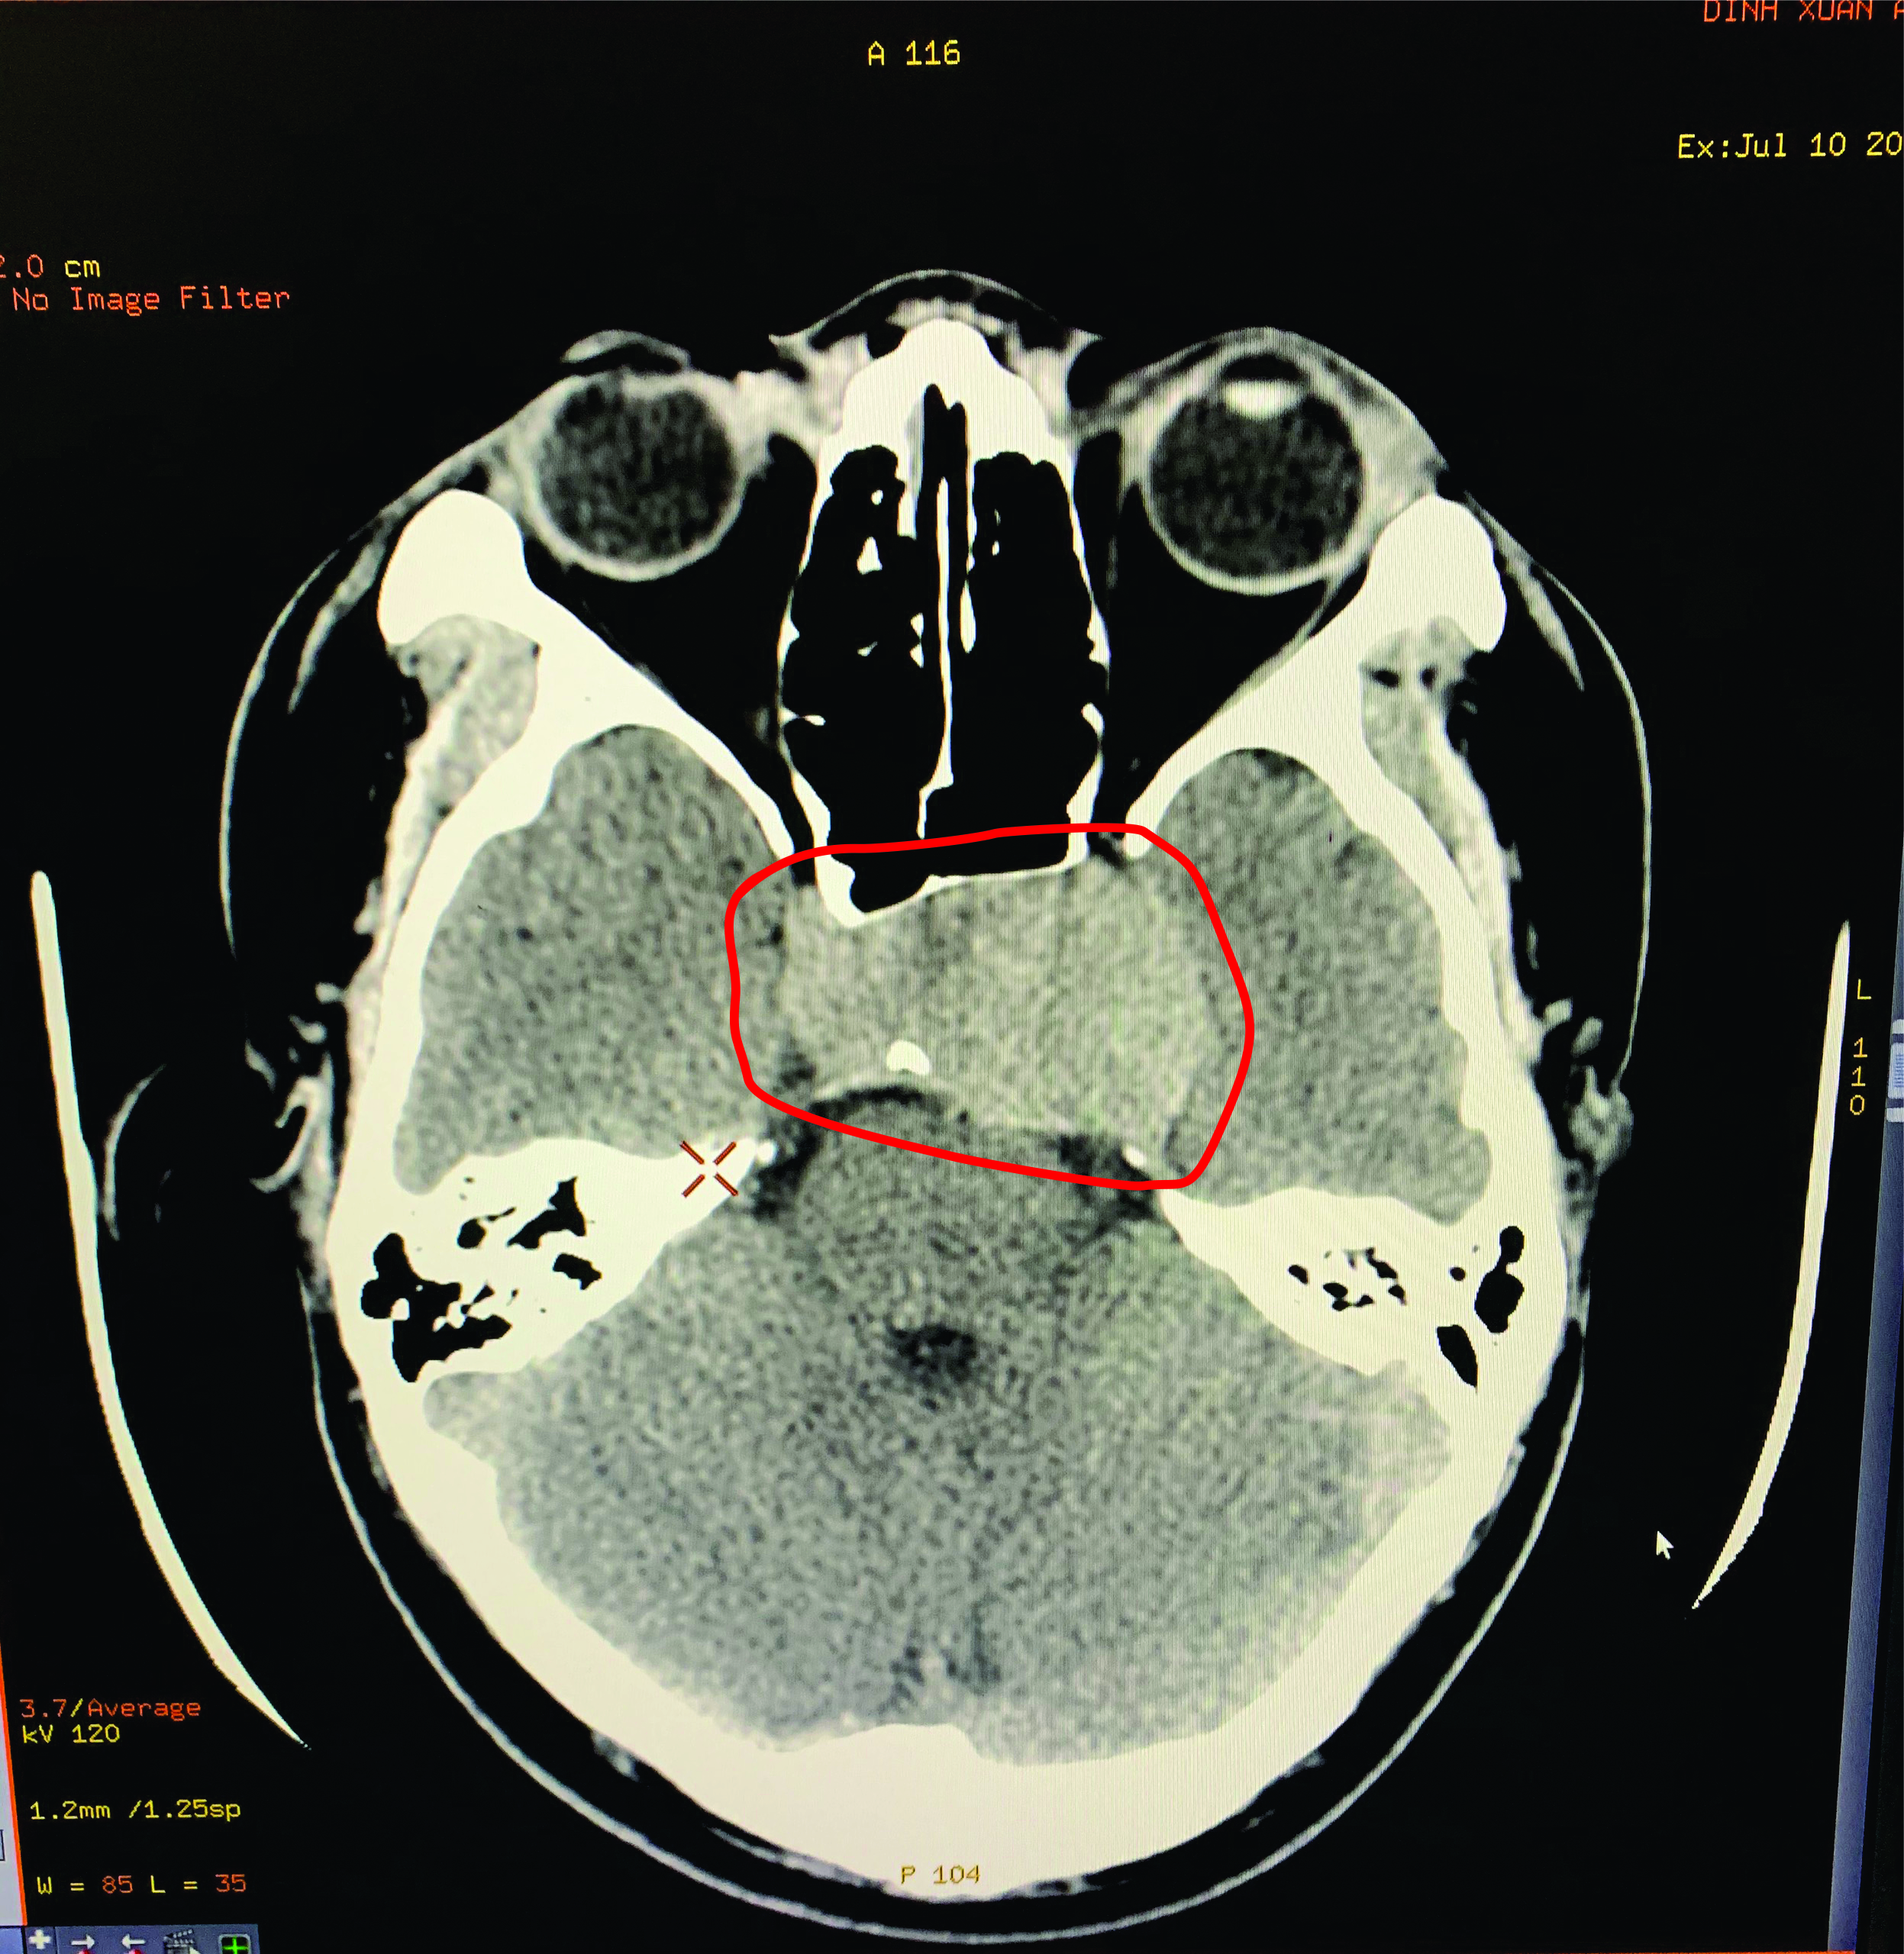

Ngày 10/7/2020, người bệnh nam Đ.X.A, 22 tuổi, đến khám tại Trung tâm Y tế huyện Yên Lập với triệu chứng đau đầu, chóng mặt, tầm nhìn hạn chế. Qua hình ảnh cắt lớp vi tính Bác sỹ Phùng Ngọc Minh – Khoa Xét nghiệm & Chẩn đoán hình ảnh phát hiện khối u tuyến yên kích thước lớn, nằm trong hố yên, chèn vào dây thần kinh thị giác.

Hình ảnh u tuyến có kích thước lớn